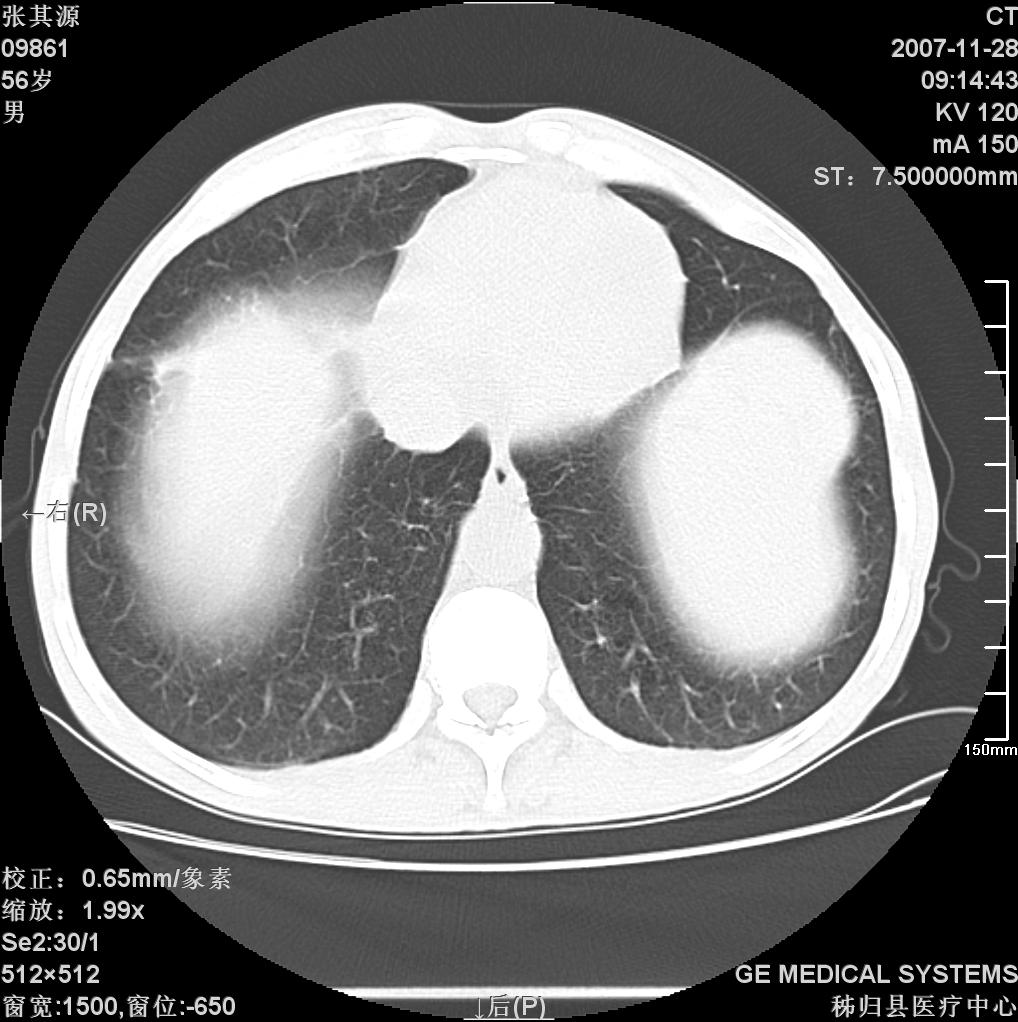

患者因阻塞性黄疸入院,发病前10天持续中等程度发烧.术前检查发现两肺弥漫性病变,请各位大虾会诊,除了考虑急性血源性肺结核外,还有其他什么疾病可能.

影像符合粟粒型肺tb改变。

胆管肿瘤确诊的话,首先考滤转移。

考虑tb不排除转移,(隆突处有肿大淋巴结,不好说是结核还是转移引起的)

两肺另见略大结节,结合病史,应考虑转移,有腹部片吗?肺内表现可有:结核?甲状腺癌肺转移?肺泡癌?

双肺多发粟粒样病灶,右肺胸膜下结节样病灶,气管前腔静脉后及隆突下均见肿大淋巴结,结合胆道肿瘤病史首先考虑转移。另外心影密度略低,时间格显示,是否有贫血?查明白再手术吧!